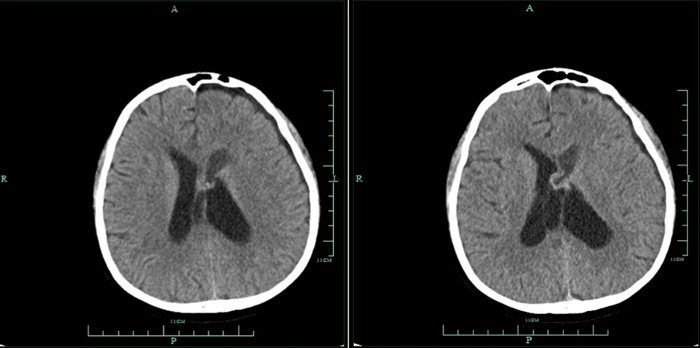

经过5个多小时的精细操作,手术团队大部分切除肿瘤,并解决了脑积水问题。术后患者恢复良好,未出现神经功能损伤。

△术后CT

△术后CT该院神经外科主任赵卫海介绍,神经内镜手术技术是近年来国内神经外科领域的重要发展方向。此次手术的成功,体现了市中心医院在微创神经外科技术上的领先水平。

医院已将此项技术纳入常规诊疗方案,未来将开展更多相关临床研究和应用,造福更多脑深部病变患者。